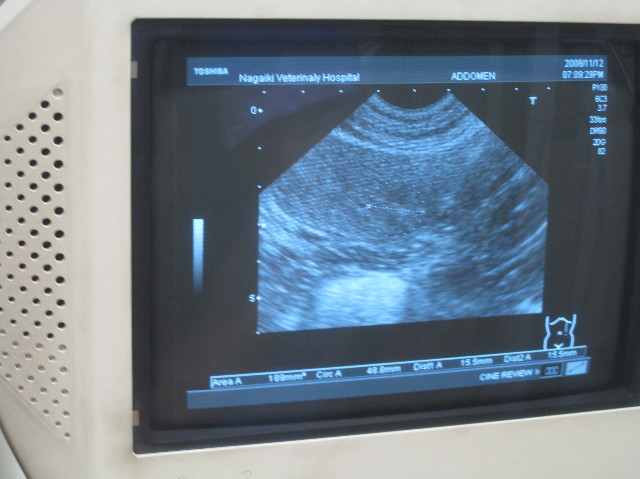

CT画像をみながら、もう一度良く説明してもらった。

それにしてもでっかい腫瘍だよね。

そんな事はわからないけれど、この後のエコーで、わりと最近できて急速に大きくなったのではないか?という雰囲気。。。

先週、先々週と2.5cmくらいだったベベちゃんの脾臓のうっ血?みたいな部分。

6日後の今日には4.3cmにも大きくなっていて先生方はびっくり。

上の黒くうつっているところが本来の正常な脾臓の組織。

CTではよくわからないけれど、うっ血と言っていた部分はもしかしたら腫瘍みたいな出っ張りかもしれない。

脾臓は血の貯蔵庫みたいなものだから、容易に一部分が倍の大きさになったり、逆に小さくなったりすることもあるらしい。

それぞれの臓器との境界を詳しくみてくださって、ベベの腫瘍は脾臓由来のものである可能性が高まった。

(CTからみるにリンパ系のものではないらしい。肛門嚢腺癌の転移の可能性もあるけれど、なんとなく違う感じ)